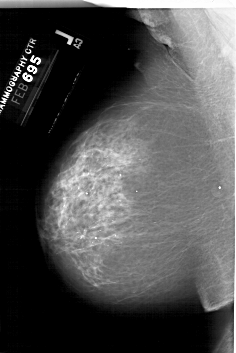

A_1999_1.LEFT_MLO

LEFT_MLO LINES 6346 PIXELS_PER_LINE 4246 BITS_PER_PIXEL 12 RESOLUTION 43.5 NON_OVERLAY